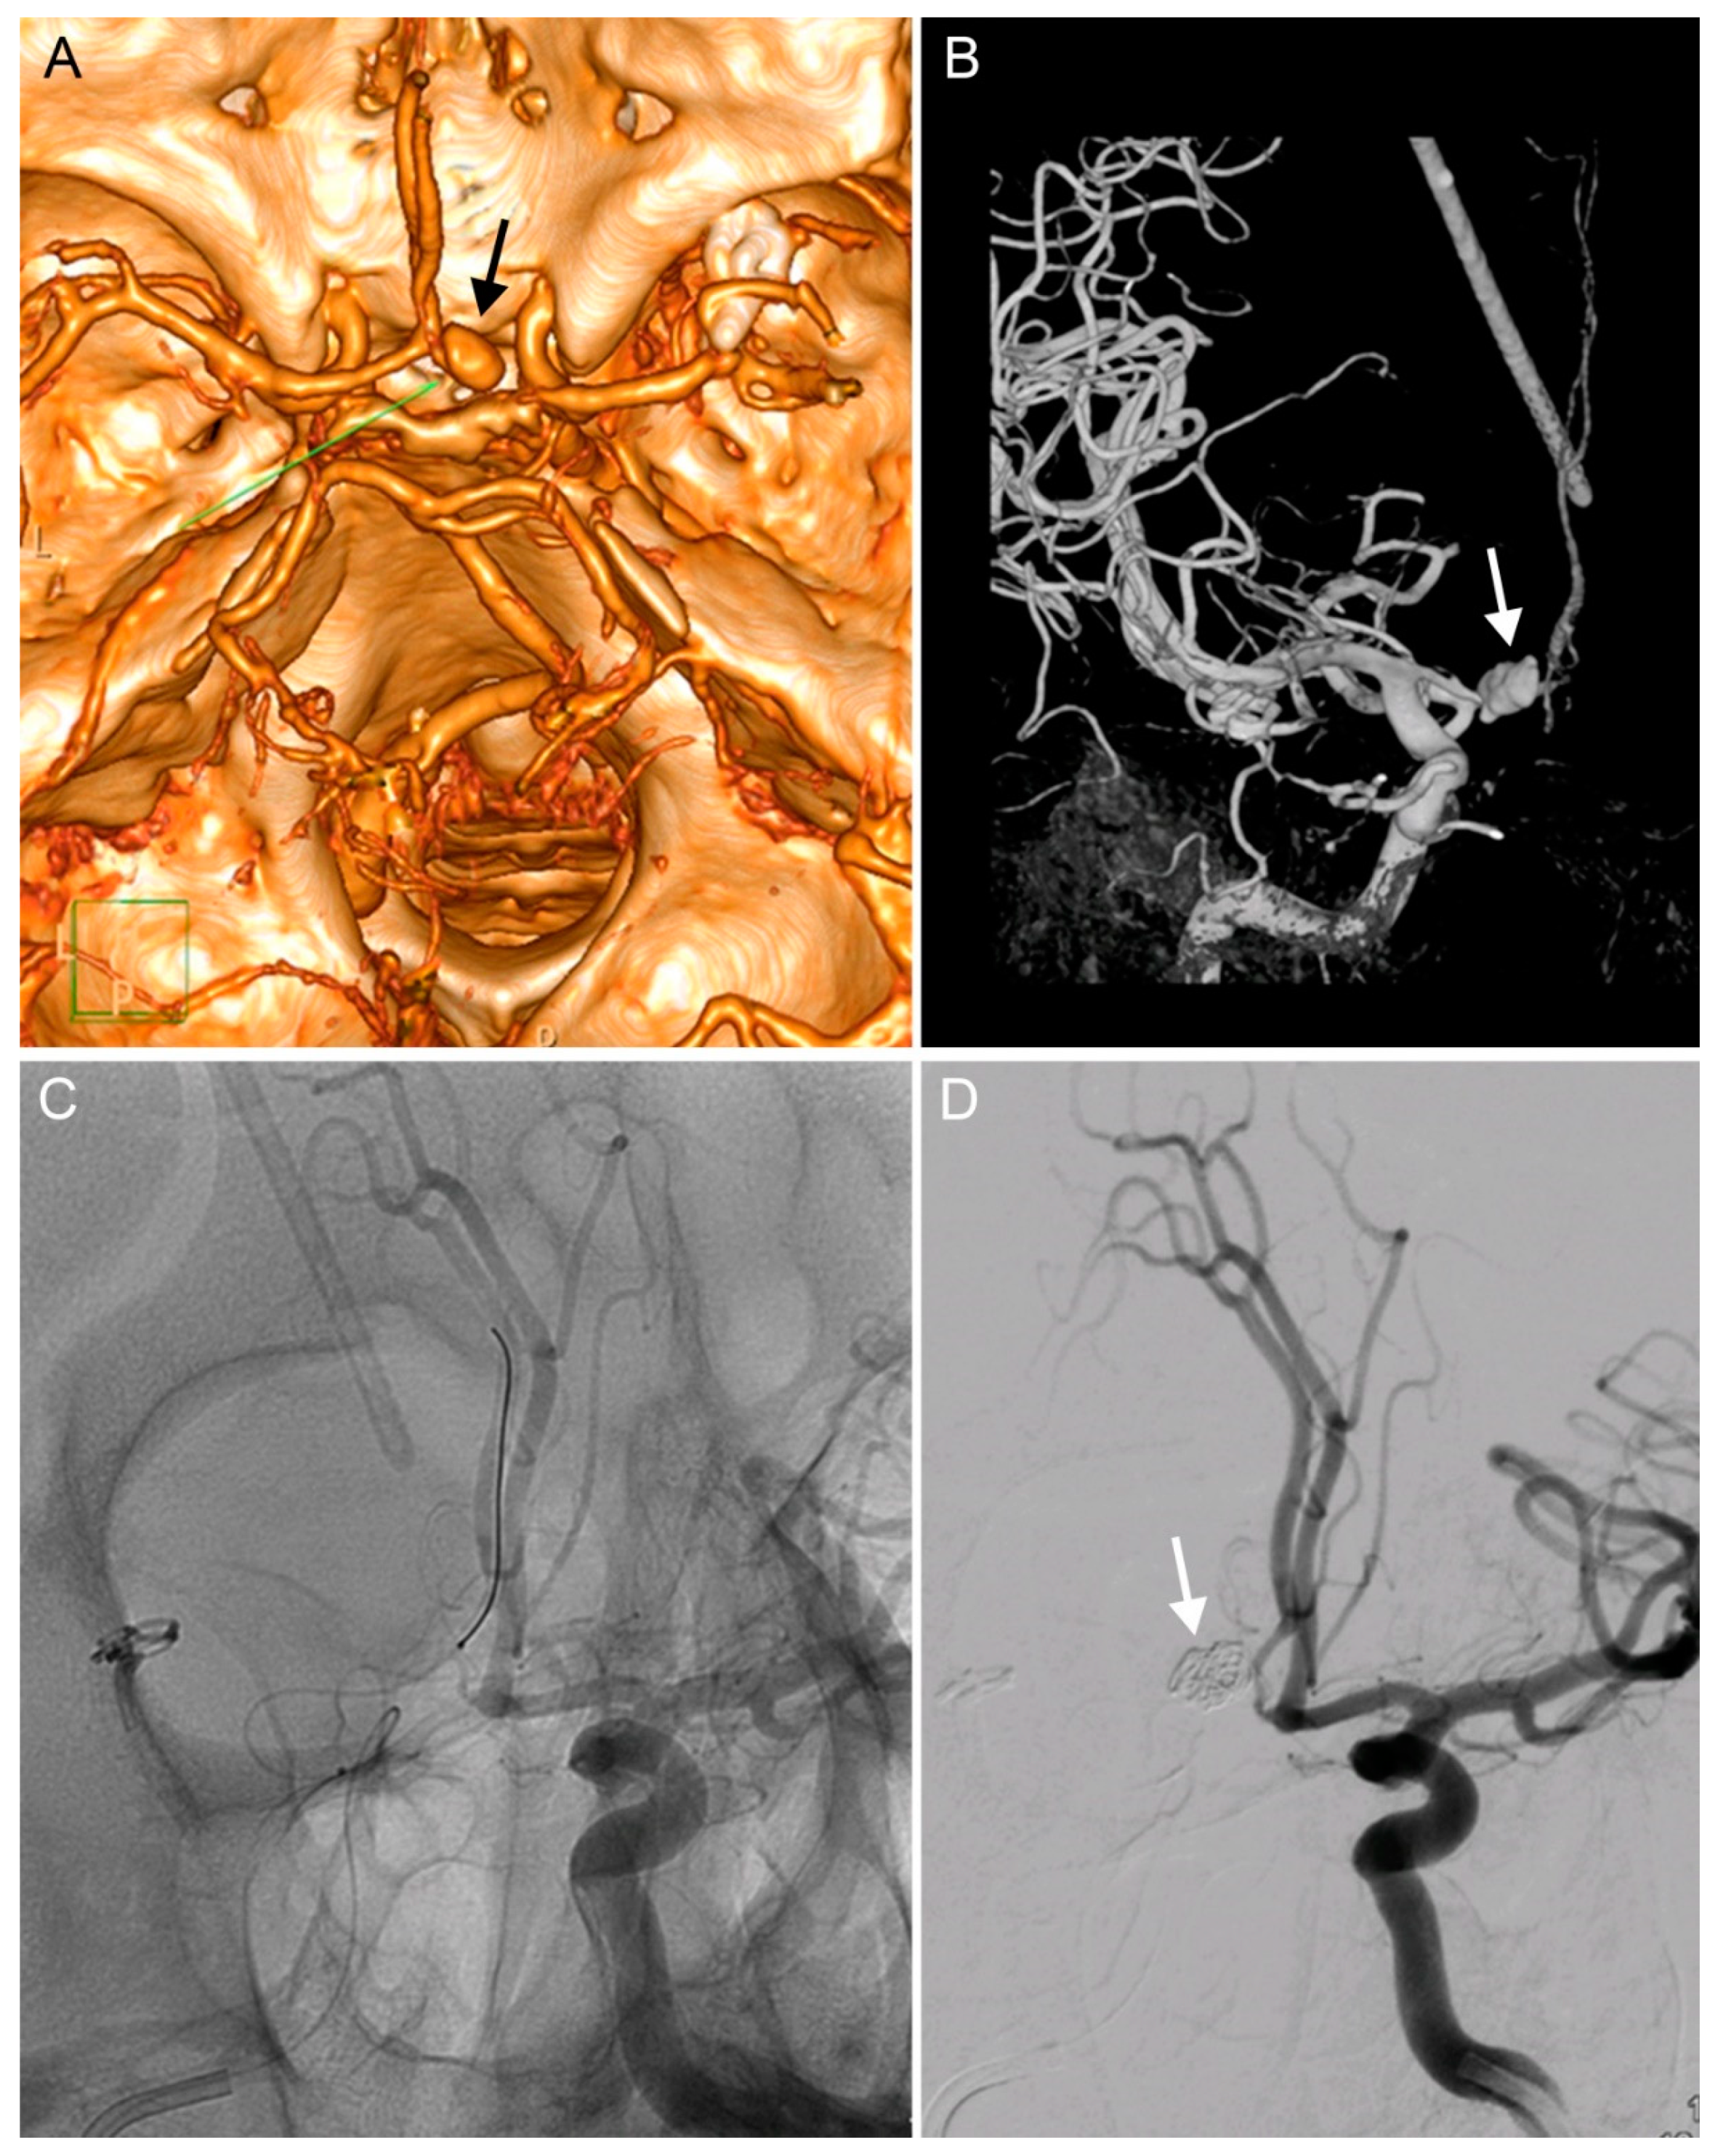

We decided to treat the pathologies immediately, which necessitated the insertion of a caval filter due to deep vein thrombosis. The following day, a ventriculo-peritoneal shunt (Certas, Medtronic) was implanted and, six days later, diagnostic angiography was performed and verified the presence of a 17 mm PSA in the distal A1 segment of the ACA (Figure 2A,B). The PSA was coiled the following day (Cosmos Complex spirals into the aneurysm dome, Target Nano in the aneurysm ostium and the A1 segment of the ACA). The patency of the ipsilateral A2-3 via the anterior communicating artery was verified in the final angiogram, which also demonstrated complete occlusion of the PSA (Figure 2C,D). No further neurological deficits developed following the endovascular procedure and the patient was successfully treated for suspected shunt meningitis (negative bacterial cultures) with meropenem. The patient was transferred to his local hospital and later released.

Figure 2. Diagnosis and endovascular treatment of an iatrogenic PSA of the A1 segment of the right anterior cerebral artery (ACA). (A). CT angiography showing a PSA of the right A1 segment (arrow). (B). The same PSA on a diagnostic digital substraction angiography (DSA, arrow) after implanting a ventriculo-peritoneal (VP) shunt. (C). An endovascular intervention for the PSA: a guidewire in the right ACA. (D). Angiography showing completed coiling of the PSA and showing patency of both A2 segments.